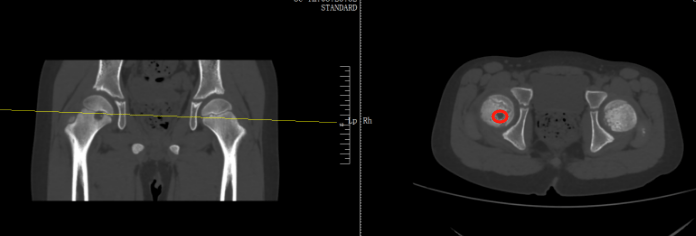

到医院就诊后被诊断为骨癌

检查后,医生发现,肿瘤直径约有20厘米,基本占满了女孩的右侧屁股,万幸还未出现远处转移,可以通过手术将肿瘤剥离那可恩普拉托姆联vs查英特贺纳比尔 。